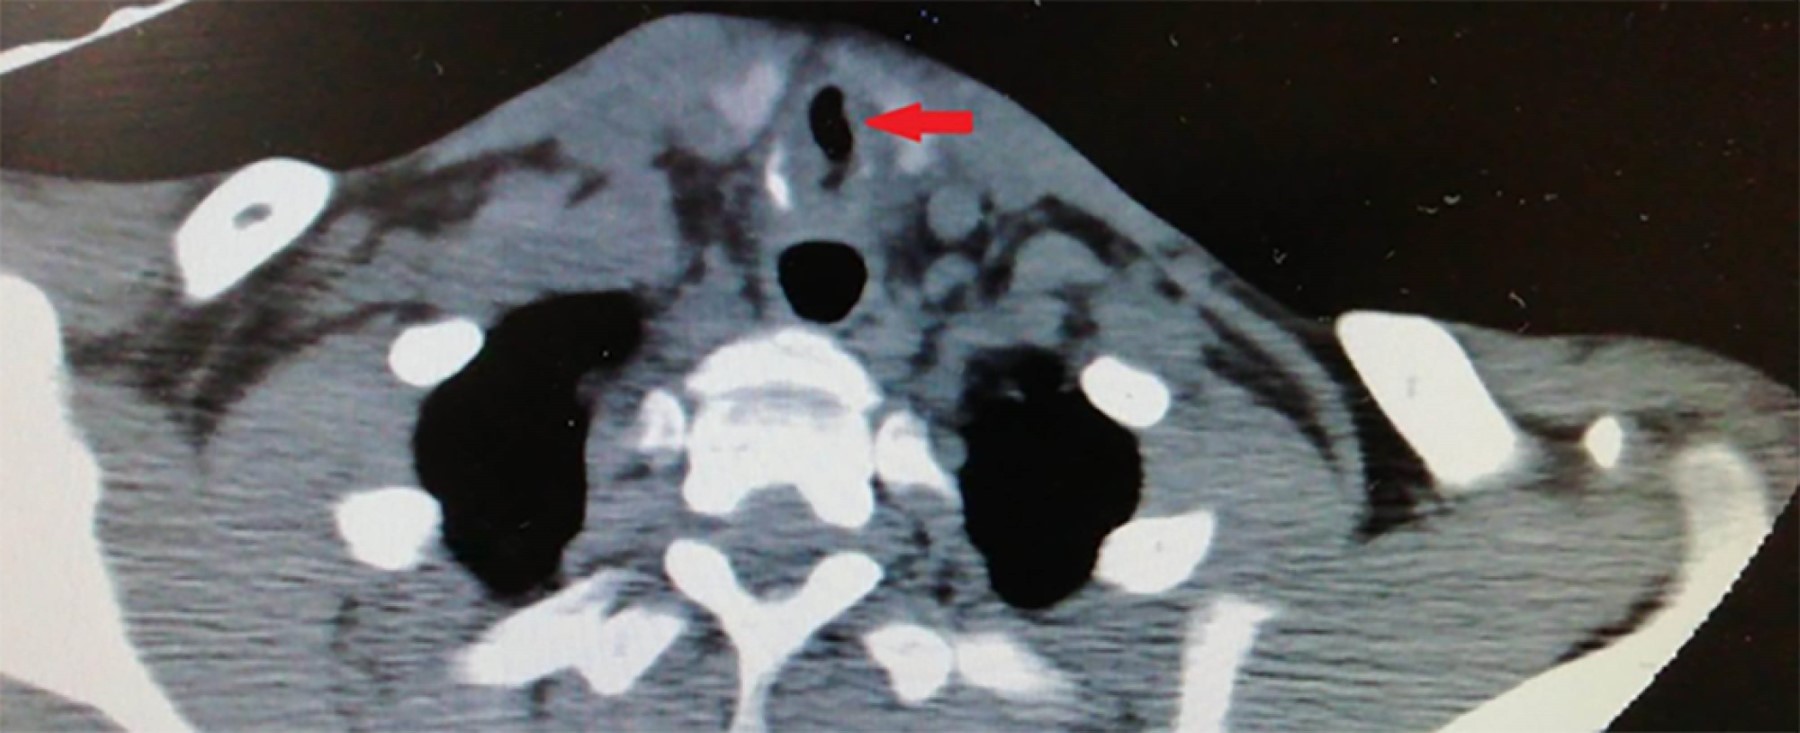

Post-intubation tracheal stenosis in patient with asymptomatic COVID-19

Postintubation tracheal stenosis is a known complication of prolonged mechanical ventilation. It is a frequent cause of tracheostomy, resection, or reconstructive surgery of the trachea. Treatment of these patients is difficult, especially if their presentation jeopardizes the permeability of the airway. We present the case of a patient with acute respiratory acidosis due to tracheal stenosis and a concomitant asymptomatic infection of COVID-19. Medical record of 5 days of mechanical ventilation for a traumatic brain injury a month before. A tracheostomy was performed with a good clinical outcome.

Figure 1

Figure 2

Figure 3